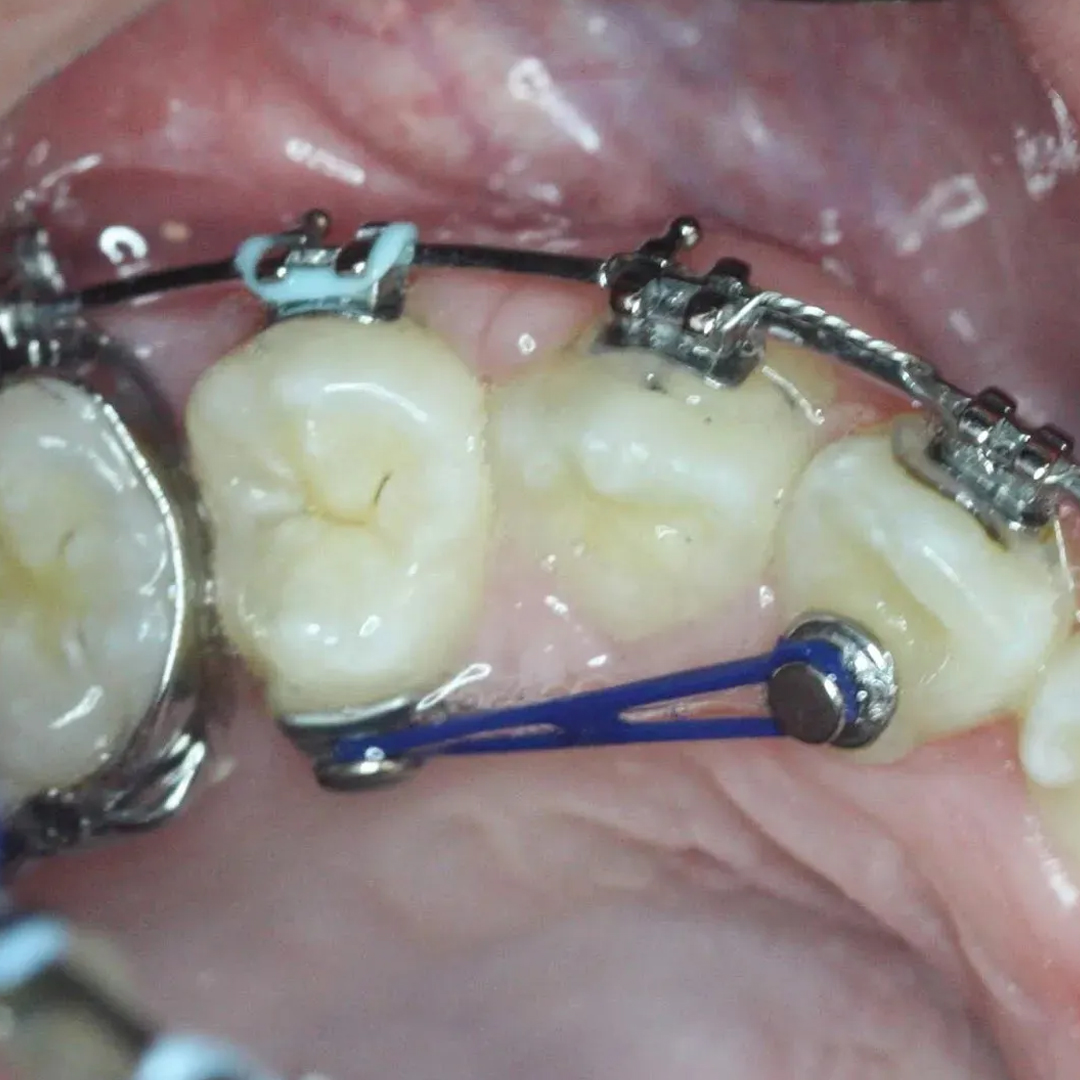

- Attachment of Accessories: Depending on the treatment goals, orthodontic accessories such as elastics, power chains, or archwires are attached to the Bondable Buttons.

- Elastic Placement: Bondable Buttons serve as anchor points for elastics, allowing orthodontists to apply forces to correct bite issues, close gaps, or achieve specific tooth movements.

A: Bondable Buttons serve as anchor points for elastics. These elastics are used to apply specific forces to correct bite issues, close gaps between teeth, or achieve precise tooth movements. The buttons ensure that the forces are applied accurately.